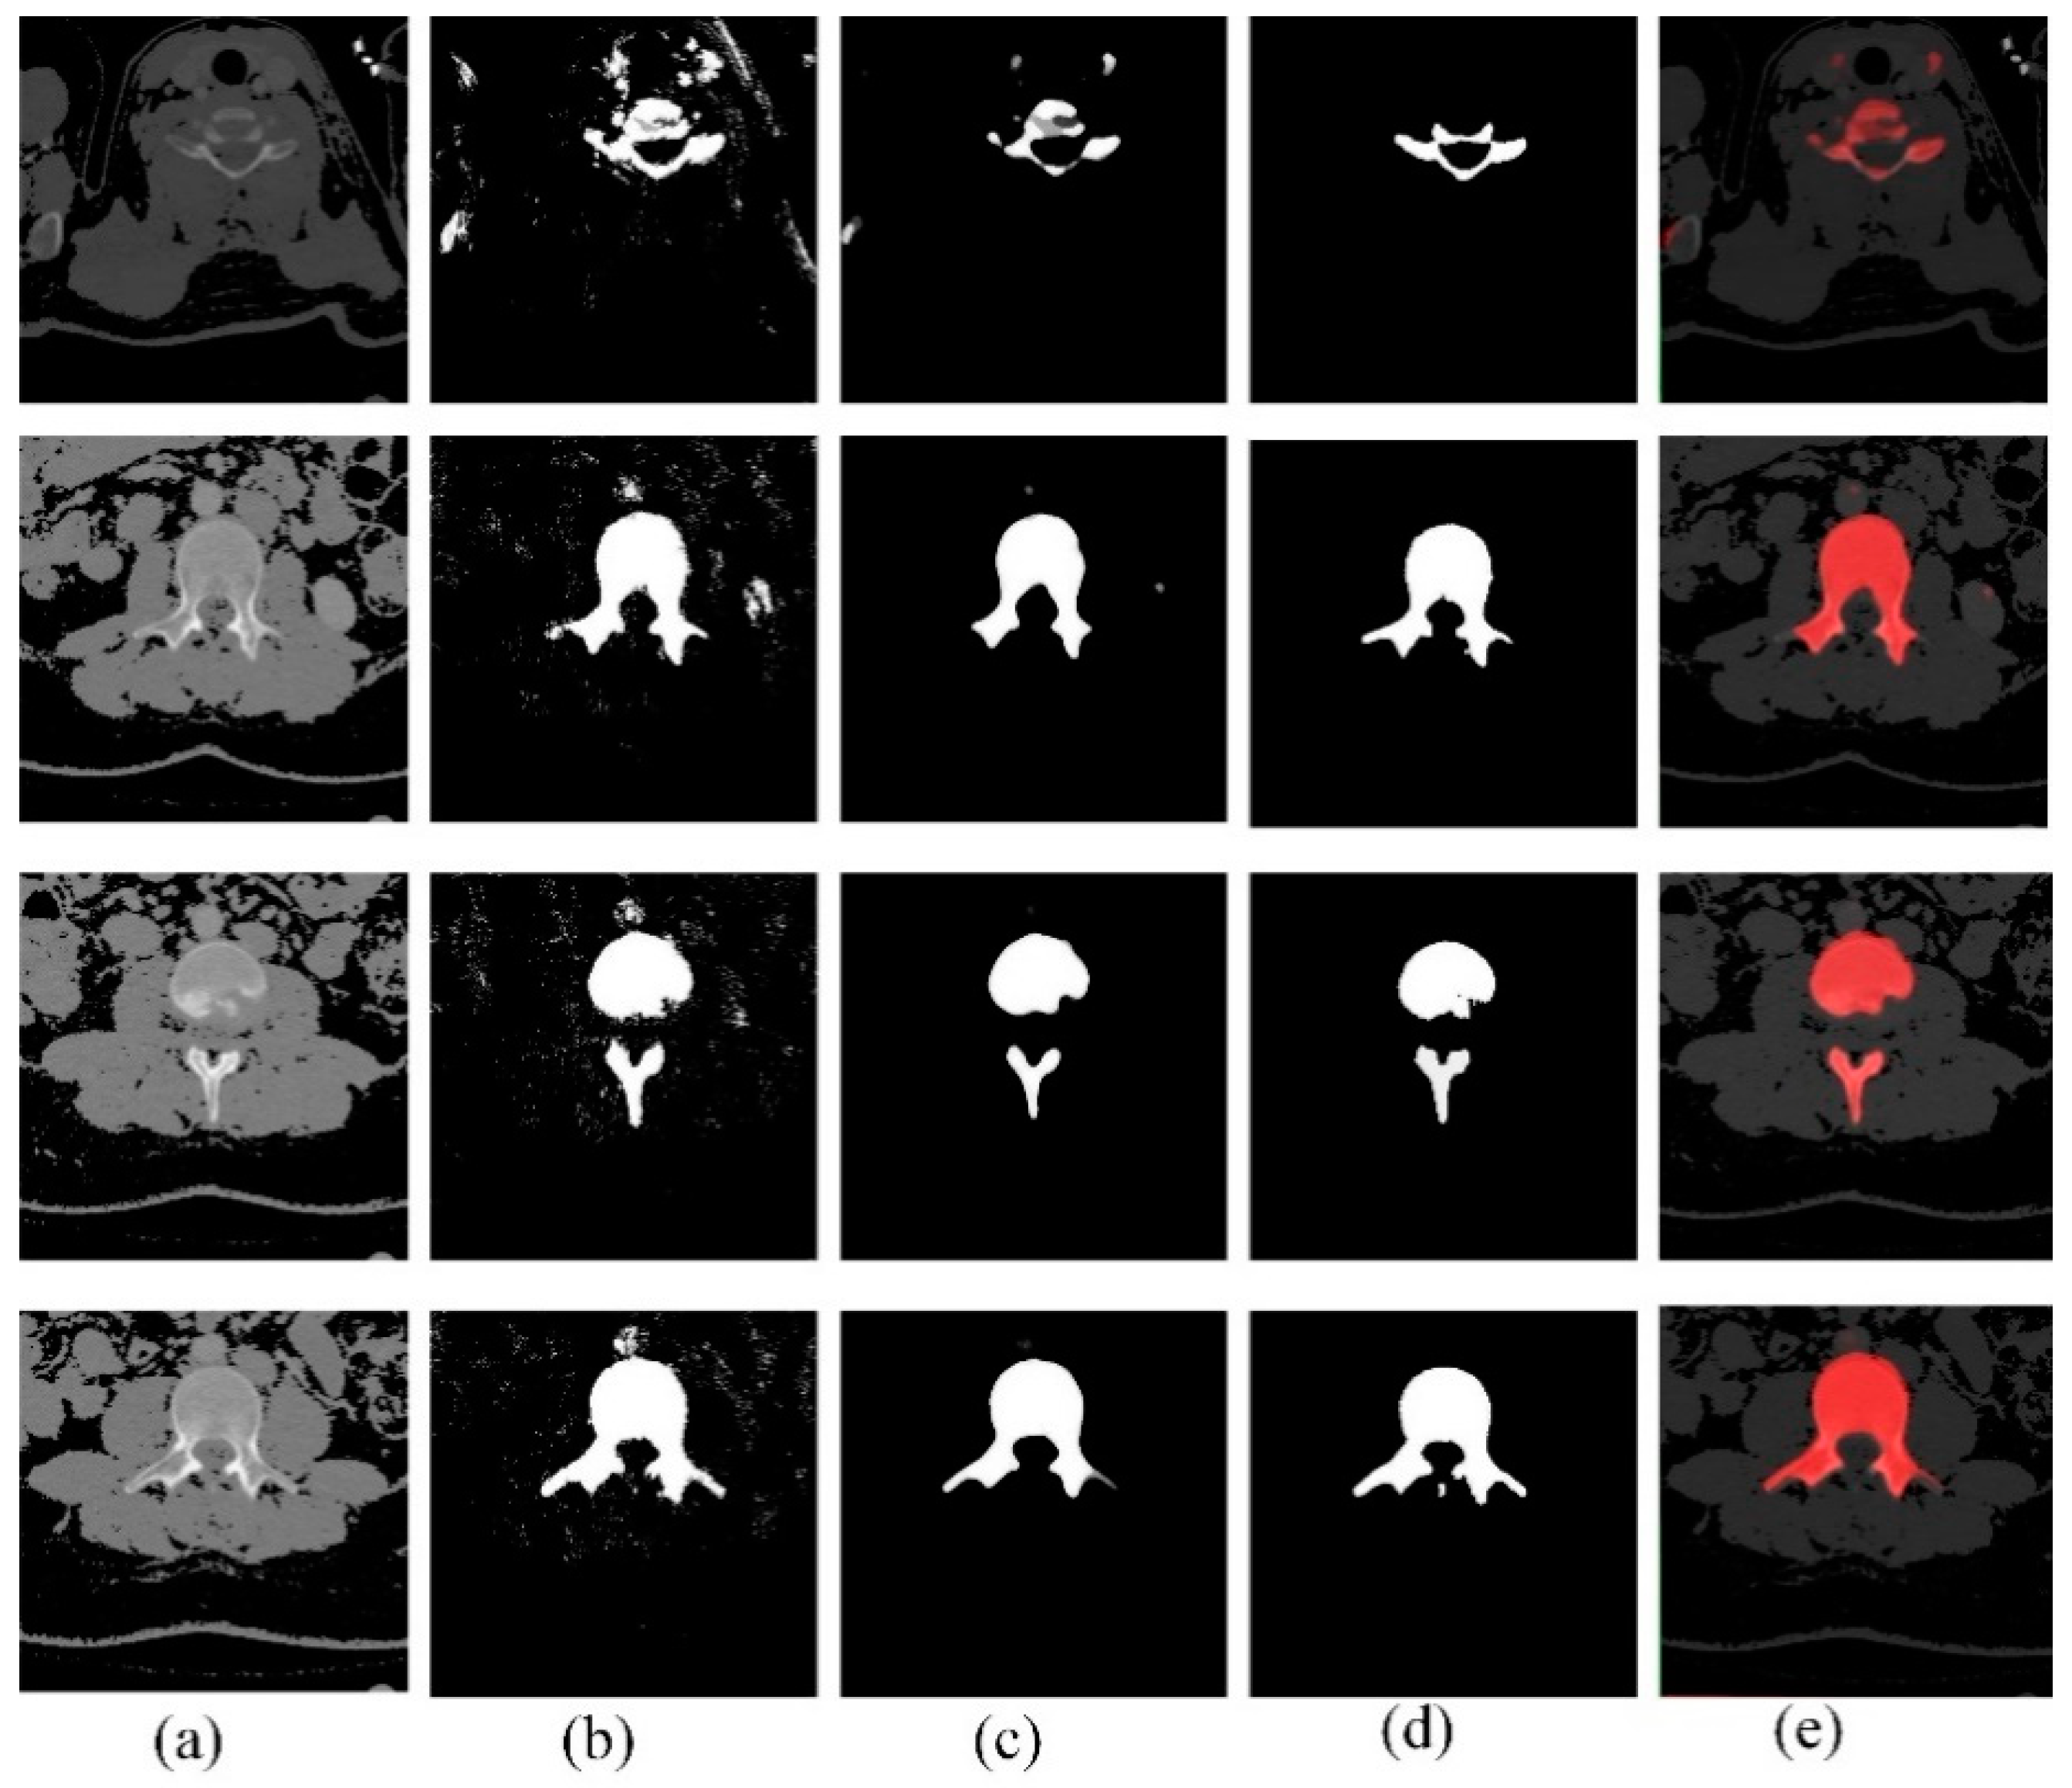

2.1. Preprocessing

2.2. Patch Generation

2.4. Segmentation